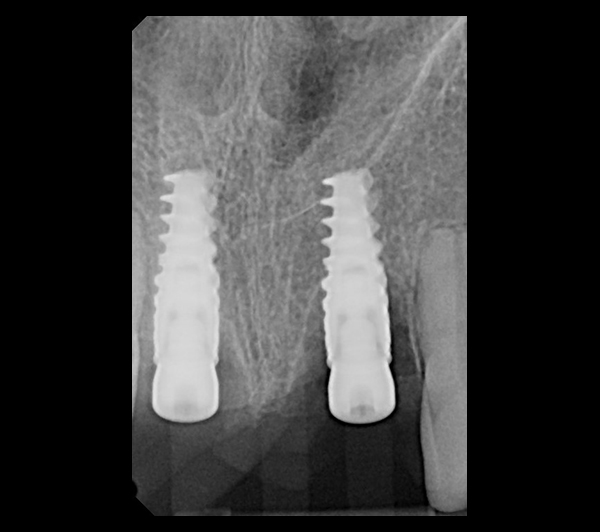

Extraction after forced eruption can allow for a much more favorable implant site compared with extraction alone. This is possible because the tension applied to the periodontal ligament during orthodontic tooth movement stimulates osteoblastic activity to induce new bone formation. As the tooth moves coronally during extrusion, soft tissue and bone attached to the periodontal fibers migrate in the same direction. As a result, forced eruption can be used to enhance the quality and quantity of both hard and soft tissue of future implant sites.

The special report presented below illustrates how orthodontic extrusion was successfully used to improve the periodontal architecture prior to the placement of two adjacent implants in the esthetic zone and thus allowed for a more ideal restorative result.